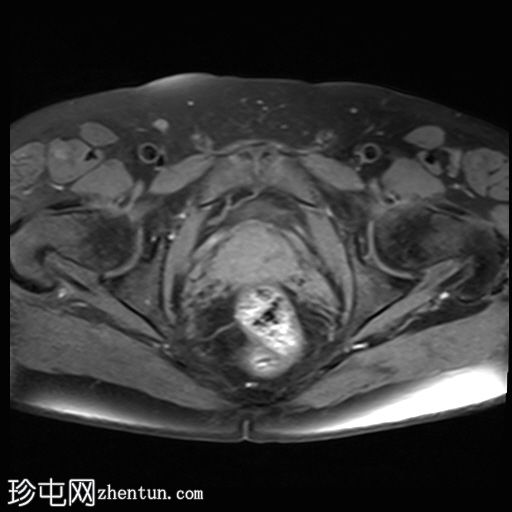

轴向位

T1时间

T1

位于5点钟和6点钟位置之间,在STIR和T2加权图像上呈高信号。

瘘管起源于括约肌间平面附近,穿过肛门内外括约肌,并延伸至左侧坐骨肛门窝。瘘管内充满液体信号,周围有轻微水肿。肛提肌上方未观察到颅骨延伸。

根据圣詹姆斯大学医院的磁共振分类系统,该病例被归类为III级左侧肛周经括约肌瘘,左侧坐骨肛门窝可见炎症改变。